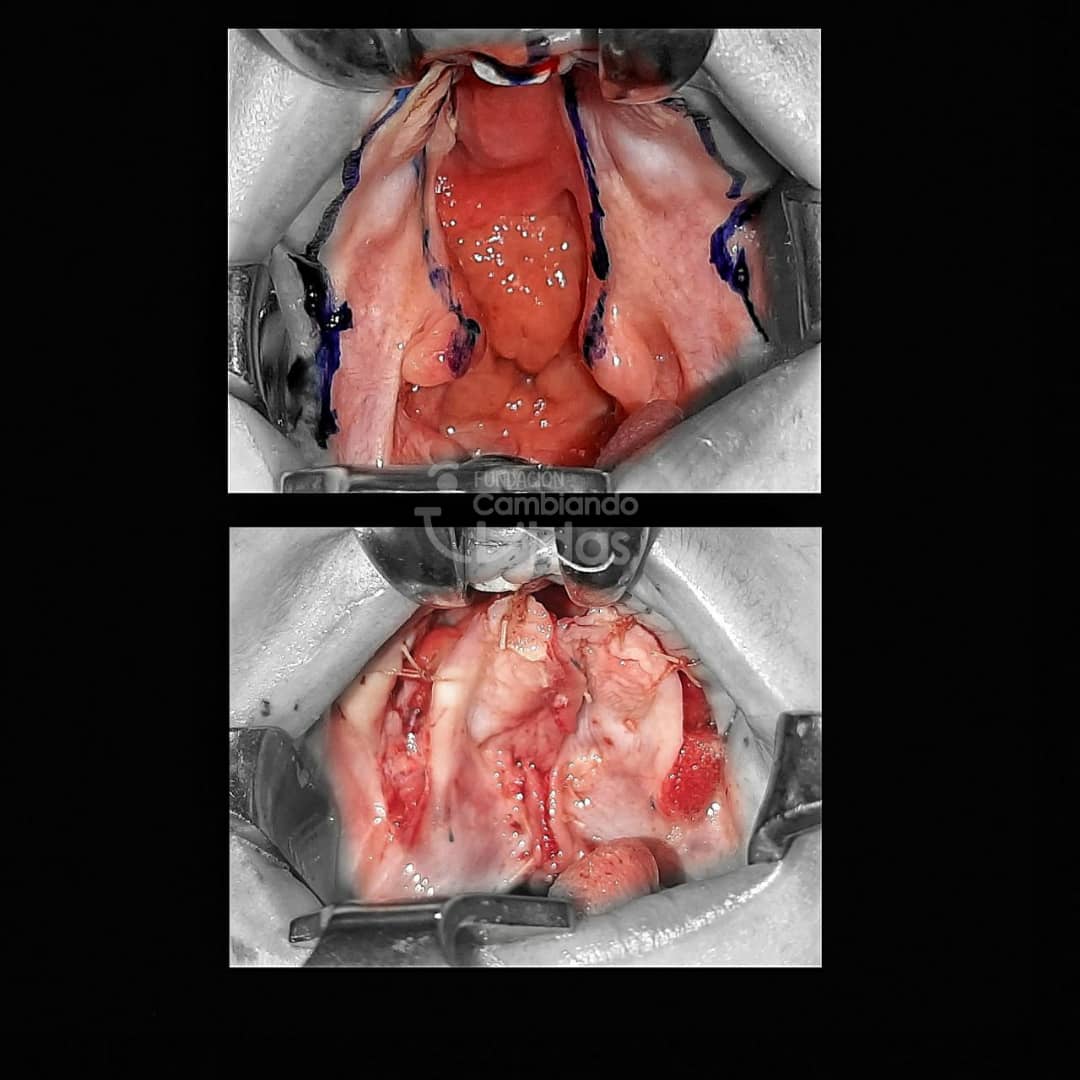

Alejandro Barrios

Intervención Quirurgica: Rinoqueiloplastia Secundaria y Palatoplastia Primaria